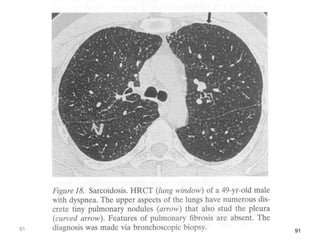

Stages

91 91

4 Stages of Pulmonary Sarcoidosis

I Bilateral hilar lymphadenopathy

and paratracheal adenopathy

55-90%

remission

II Mediastinal adenopathy with

pulmonary parenchymal

involvements

40-70%

III Pulmonary parenchymal without

adenopathy

10-20%

IV Pulmonary fibrosis with

honeycombing

0-5%

Clinical Presentation • Mostpatients have the pulmonary manifestations, most commonly presenting with incidental findings on CXR. • Interstitial disease • Symptoms include dry cough, dyspnea, and chest discomfort • Unpredictable course

4 Stages ofPulmonary Sarcoidosis I Bilateral hilar lymphadenopathy and paratracheal adenopathy 55-90% remission II Mediastinal adenopathy with pulmonary parenchymal involvements 40-70% III Pulmonary parenchymal without adenopathy 10-20% IV Pulmonary fibrosis with honeycombing 0-5%